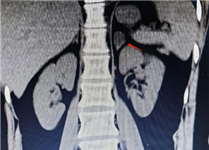

肾上腺CT正常表现

1.形态:形态各异;右侧:斜线状、倒“V”、倒“Y”形;左侧: 倒“V”、倒“Y”形或三角形;三维重建呈叶状。

2.大小: 侧支厚度<10mm;侧支厚小于同侧膈肌脚,面积小于150mm。

3.密度: 均匀,边缘光滑,无外凸结节。

4.强化: 均匀,边缘光滑。

肾上腺腺瘤CT表现

1.肾上腺腺瘤发生于肾上腺皮质,含脂质;

2.直径多小于3cm;

3.CT值<10HU;

4.出血、坏死、囊变少见;5.CT增强:早期快速廓清